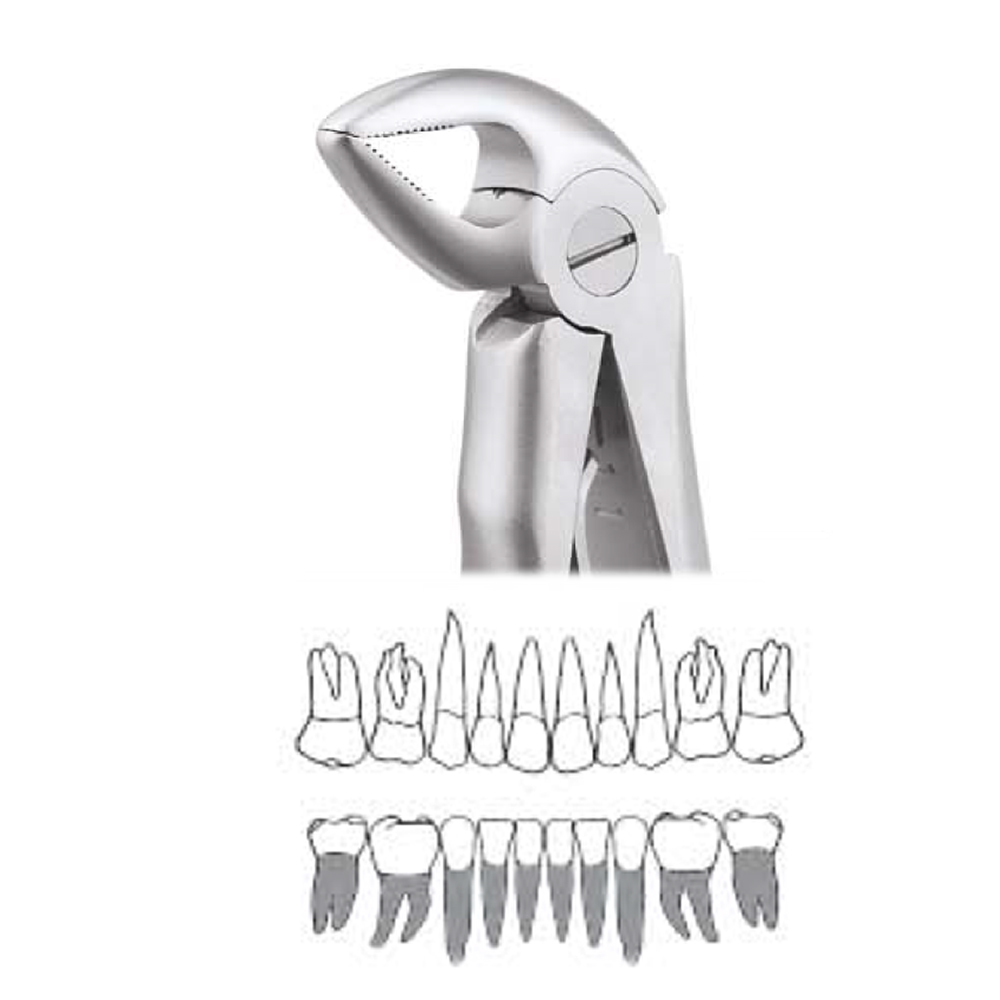

Pedo Extraction Forceps: These specialized forceps are designed to extract deciduous (baby) teeth gently. They have smaller, anatomically adapted beaks that fit comfortably around the smaller roots of baby teeth, reducing the risk of trauma during extraction. The handles are designed for easy grip and better control, ensuring a safe and efficient extraction process.

Pedo American Forceps: These forceps are designed to grip and extract deciduous teeth that are mobile or need removal. They have unique beak designs that cater to the varying shapes and sizes of baby teeth, providing a secure hold for extraction while minimizing any discomfort for the child.